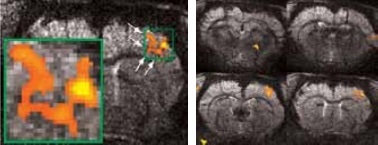

Matrices up to 256 x 256 were obtained with a four-element array coil, resulting in 75 x 75 x 1000 μm3 resolution. The activation becomes more resolved at this high resolution and allows the detection of sub-structures and shape in thalamus areas S1 and S2, as shown in Figure 3.

High resolution BOLD activation at 11.7 Tesla using the four-element array coil with a resolution of 75 x 75 x 1000 μm3 for detection of (left) sub-structures within S1, and activation within other regions along the neuronal pathway: S2 and thalamus

Figure 3. High resolution BOLD activation at 11.7 Tesla using the four-element array coil with a resolution of 75 x 75 x 1000 μm3 for detection of (left) sub-structures within S1, and activation within other regions along the neuronal pathway: S2 and thalamus. Image Credit: Bruker BioSpin Group